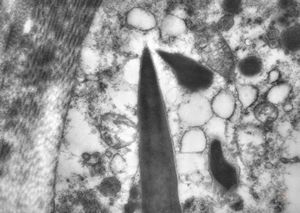

M, 43y. | myeloid leukemia … Auer bodies

M, 43y. | myeloid leukemia … Auer bodies

M, 43y. | myeloid leukemia … Auer bodies